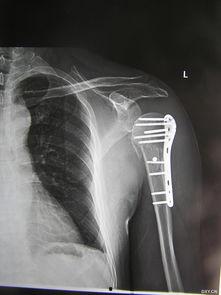

1. 手术过程视频:这类视频详细展示了手术的整个过程,包括麻醉、手术器械、手术步骤等。通过这些视频,你可以直观地了解手术的全貌。

2. 术前术后对比视频:这类视频展示了患者手术前后的变化,让你对手术效果有一个直观的认识。

成人肩膀内扣手术的效果因人而异,一般来说,手术后的肩部外观和功能都会得到明显改善。部分患者甚至可以达到完美效果。